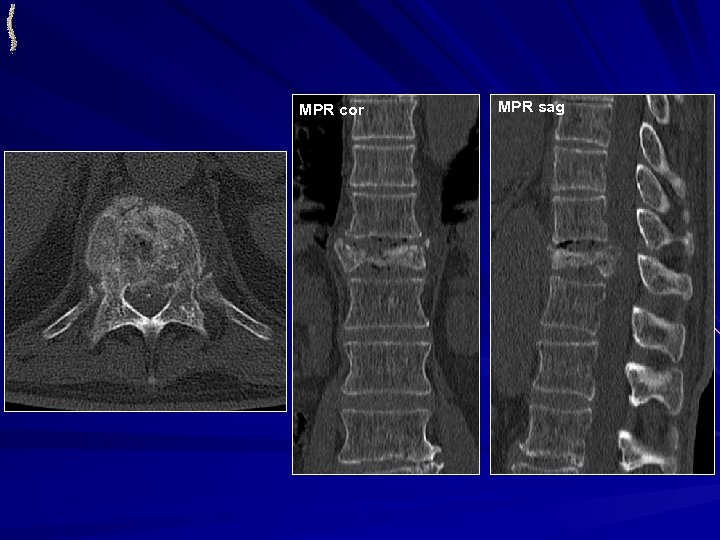

МЕТАСТАЗЫ РАКА ПРЕДСТАТЕЛЬНОЙ ЖЕЛЕЗЫ • НАИБОЛЕЕ ЧАСТО ВСТРЕЧАЕМЫЕ МЕТАСТАЗЫ СОЛИДНОЙ ОПУХОЛИ У МУЖЧИН • НАИБОЛЕЕ ЧАСТО ПОРАЖАЕТСЯ ОСЕВОЙ СКЕЛЕТ • В ОЦЕНКЕ ЭФФЕКТА ЛЕЧЕНИ КРАЙНЕ НЕОБХОДИМ ФУНКЦИОНАЛЬНЫЙ МЕТОД • КТ: ü Костная деструкция преимущественно пластического типа (до 80%), литическая деструкция встречается реже ü Множественность поражения • МРТ: ü Множественность поражения ü Неоднородная солидная структура очагов

MPR cor MPR sag